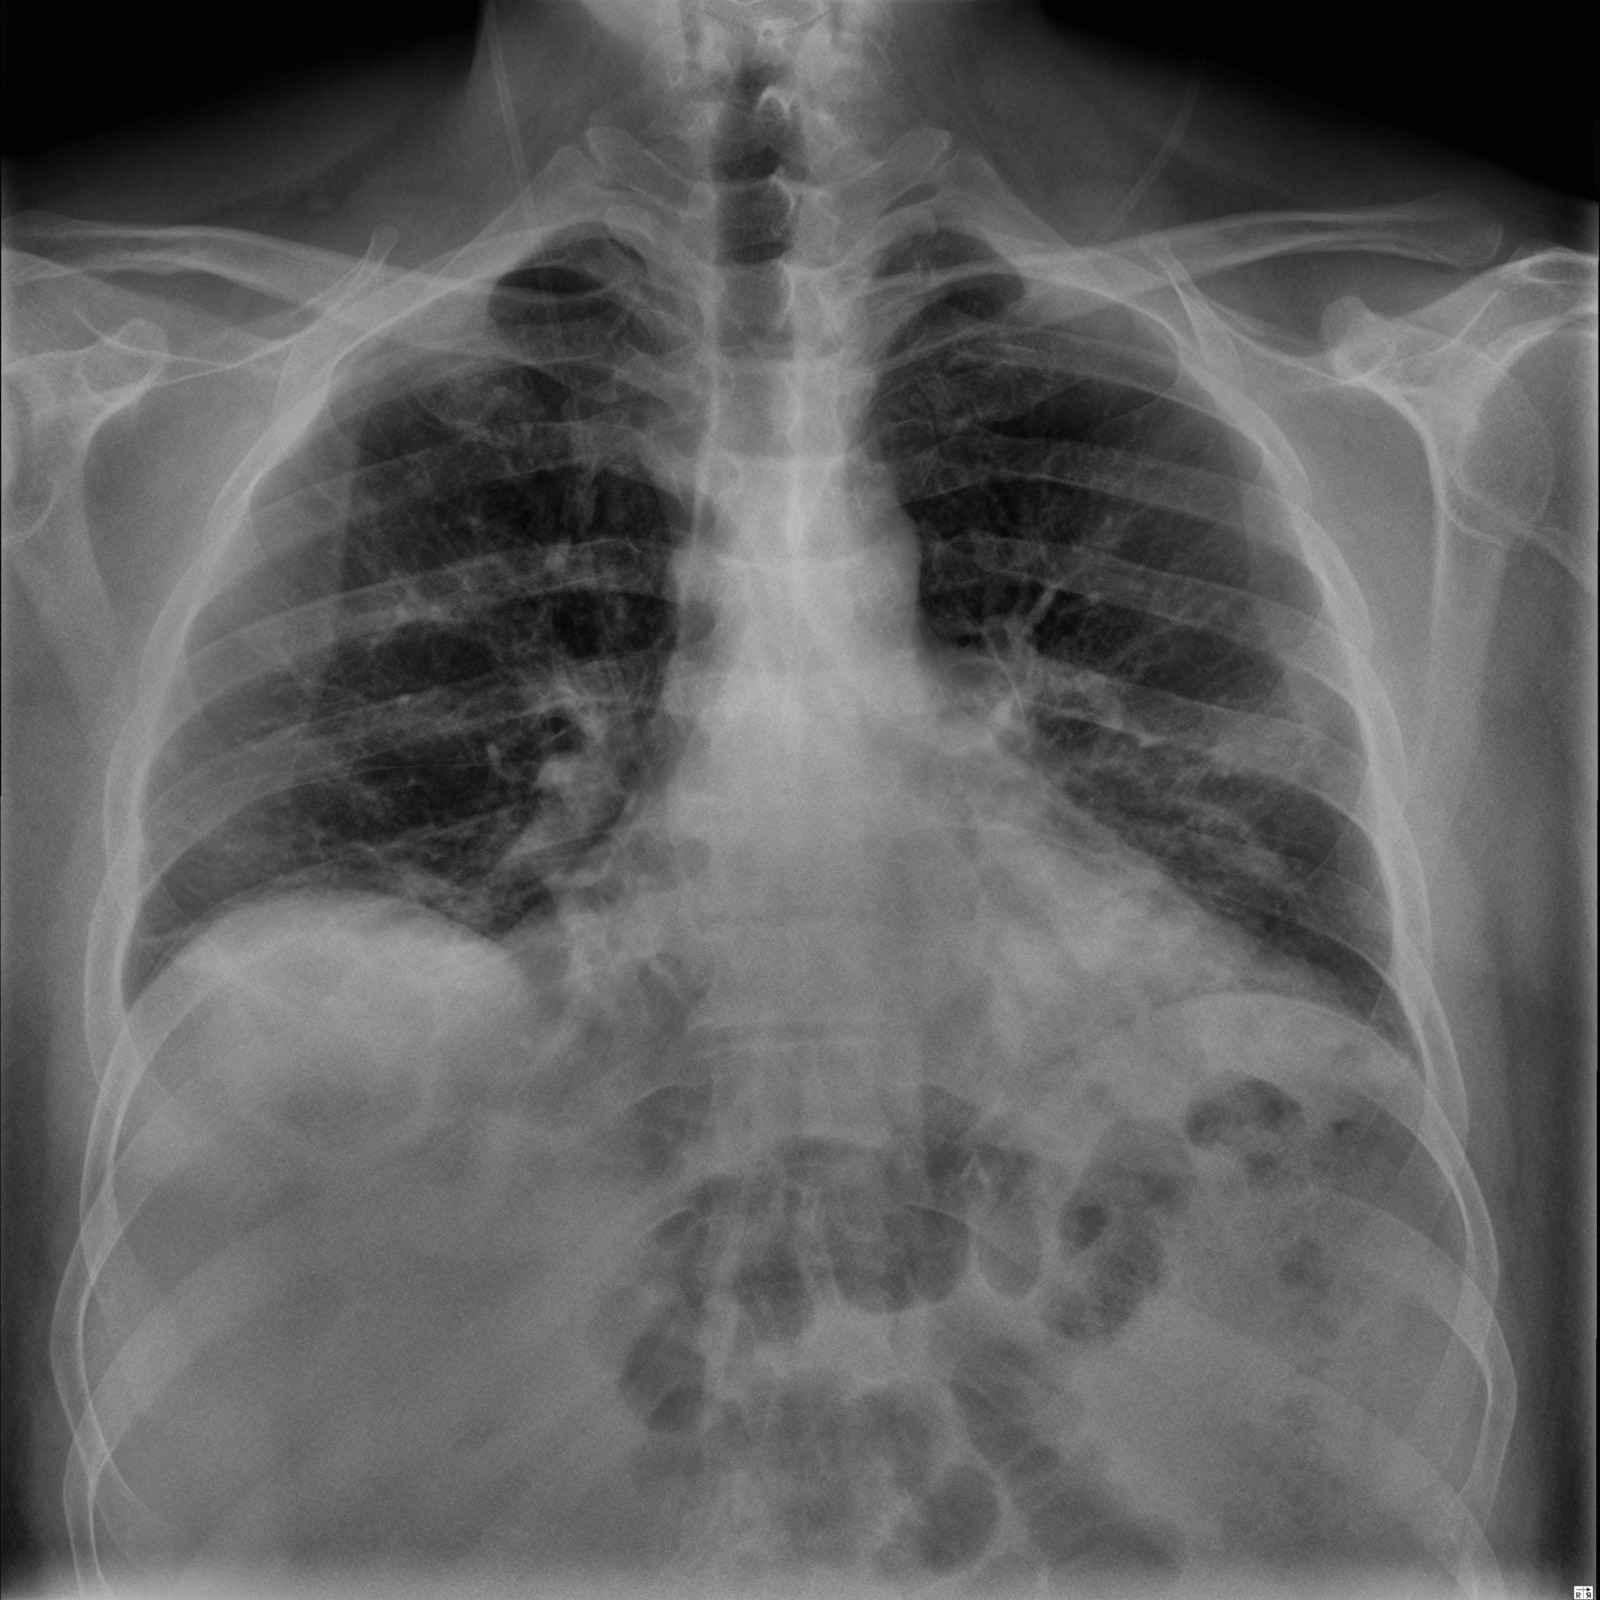

The pandemic has changed our lifestyle and until today it is affecting us, and it is necessary to know every information to keep us and our loved ones safe. With the virus mutating and increased cases of asymptomatic cases now COVID can be being detected using the chest x-rays as it affects the respiratory system first. According to LSU radiologists, these chest x-rays can be used for rapid diagnosis where there are limited testing and delayed results. And as we all know prevention is better than cure with a lot of advice from everyone there is a lot of confusion over the right and spam news. There is a need for expert advice, current news, and rapid diagnosis.

Virtual communication is the new future. In order to help the nurses, patients, and doctors in an effective way, we have created an application that predicts whether a person has COVID or not using Xray inputs from the user and giving advice on the results, The application also gives all the latest information on COVID-19, the preventions following the CDC guidelines, the statistics of COVID-19 cases, and an easy platform to contact doctors to seek advice virtually.

We used cloud technologies for our applications The model used for COVID prediction was developed using Google’s vision API which achieved a 91% accuracy. Then we designed the front end of the application using Vue-js and HTML. The application is hosted using Google's firebase using its cloud function and user authentication services.